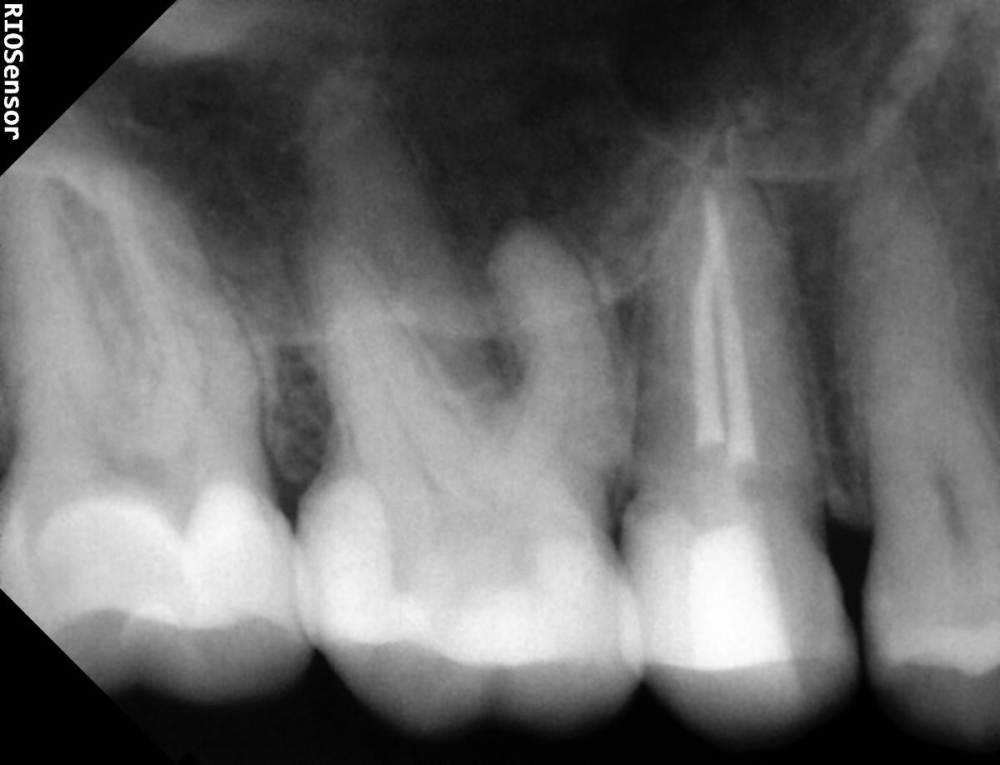

Александра117 Опубликовано 19 ноября, 2022 Поделиться Опубликовано 19 ноября, 2022 Всем Привет! Месяц назад лечила зуб верхнюю 5ку. Депульпировали и Пломбировали каналы гуттаперчей. На момент лечения в зубе уже была боль. Был поставлен диагноз пульпит. Но прошел уже месяц и боль в зубе сохраняется , при этом почти точно такая же как и до лечения. Боль постоянная ноющая средней интенсивности. Я думала это первое время после лечения такая боль будет. Но месяц прошел, а боль не уходит. Немного предыстории этого зуба: Зуб этот меня вообще не беспокоил изначально. Я пришла 12.09.2022 на прием, чтобы вылечить кариес. Стоматолог рассверлил и запломбировал. Но сказал, что очень глубокий кариес был, но решил пока сохранить пульпу и наблюдать. После лечения появились боли в зубе ,но терпимые. Через две недели боли усилились. Я пришла на прием снова с этим вопросом. Врач сказал, что после лечения глубокого кариеса могут быть боли, надо ещё понаблюдать. Ещё через пару неделю боль не проходила. Была довольно сильной. Врач принял решение депульпировать зуб. Лечение я проходила под микроскопом у опытного эндодонтиста. Именно у него я уже до этого лечила каналы у нескольких других зубов, и все было нормально. Но также это в в первый раз такое случилось, что боли такие сохраняются в течение месяца после лечения. После лечения врач сказал, что зуб меня беспокоить не должен больше. Сказал, что было лечение неосложненного пульпита. Но он беспокоит вот уже месяц. Вообще это у меня впервые, чтобы была боль в зубе и на момент лечения и после лечения каналов. До этого до болей в зубе дело не доходило. Пролечивалось раньше. Сделала свежие снимки Рентен через месяц после Лечения, их прилагаю сюда. По снимку видно, что каналы пройдены полностью до конца. Материал за Пределы Корня не выведен. Найдены все каналы. Их у меня в верхних пятерках их по два. Как и видно по КТ. Скажите, что это может быть? И что Можно сделать? Требует ли эта ситуация какого то срочного вмешательства или можно ещё наблюдать? Может ли это быть периодонтит, при том что на снимке в прикорневых тканях все спокойно? Ещё на внешней стороне зуба есть две белые трещины. Как раз на границе пломбы и стенки Зуба. В этом месте если трогать языком очень шершавая поверхность. Также, можете сказать, эти трещины это трещины Эмали или может быть что и более глубокие Трещины? ( Фото трещин тоже прилагаю) Ссылка на комментарий

Doc Опубликовано 19 ноября, 2022 Поделиться Опубликовано 19 ноября, 2022 А какого характера боли? Самопроизвольные, на холодное-горячее, острые или не очень, ночные-дневные, длительные или кратковременные? Это может иметь диагностическую ценность. Между пятеркой и шестеркой на снимке есть подозрение на кариес корня, но по этим снимкам сложно сказать что-то определенное. Ссылка на комментарий

Doc Опубликовано 20 ноября, 2022 Поделиться Опубликовано 20 ноября, 2022 На пятерке почти точно, на шестерке сложно сказать по этому снимку, но подозрение есть тоже. Если там есть кариес корня, то он вполне может перейти в пульпит и так болеть. Ссылка на комментарий